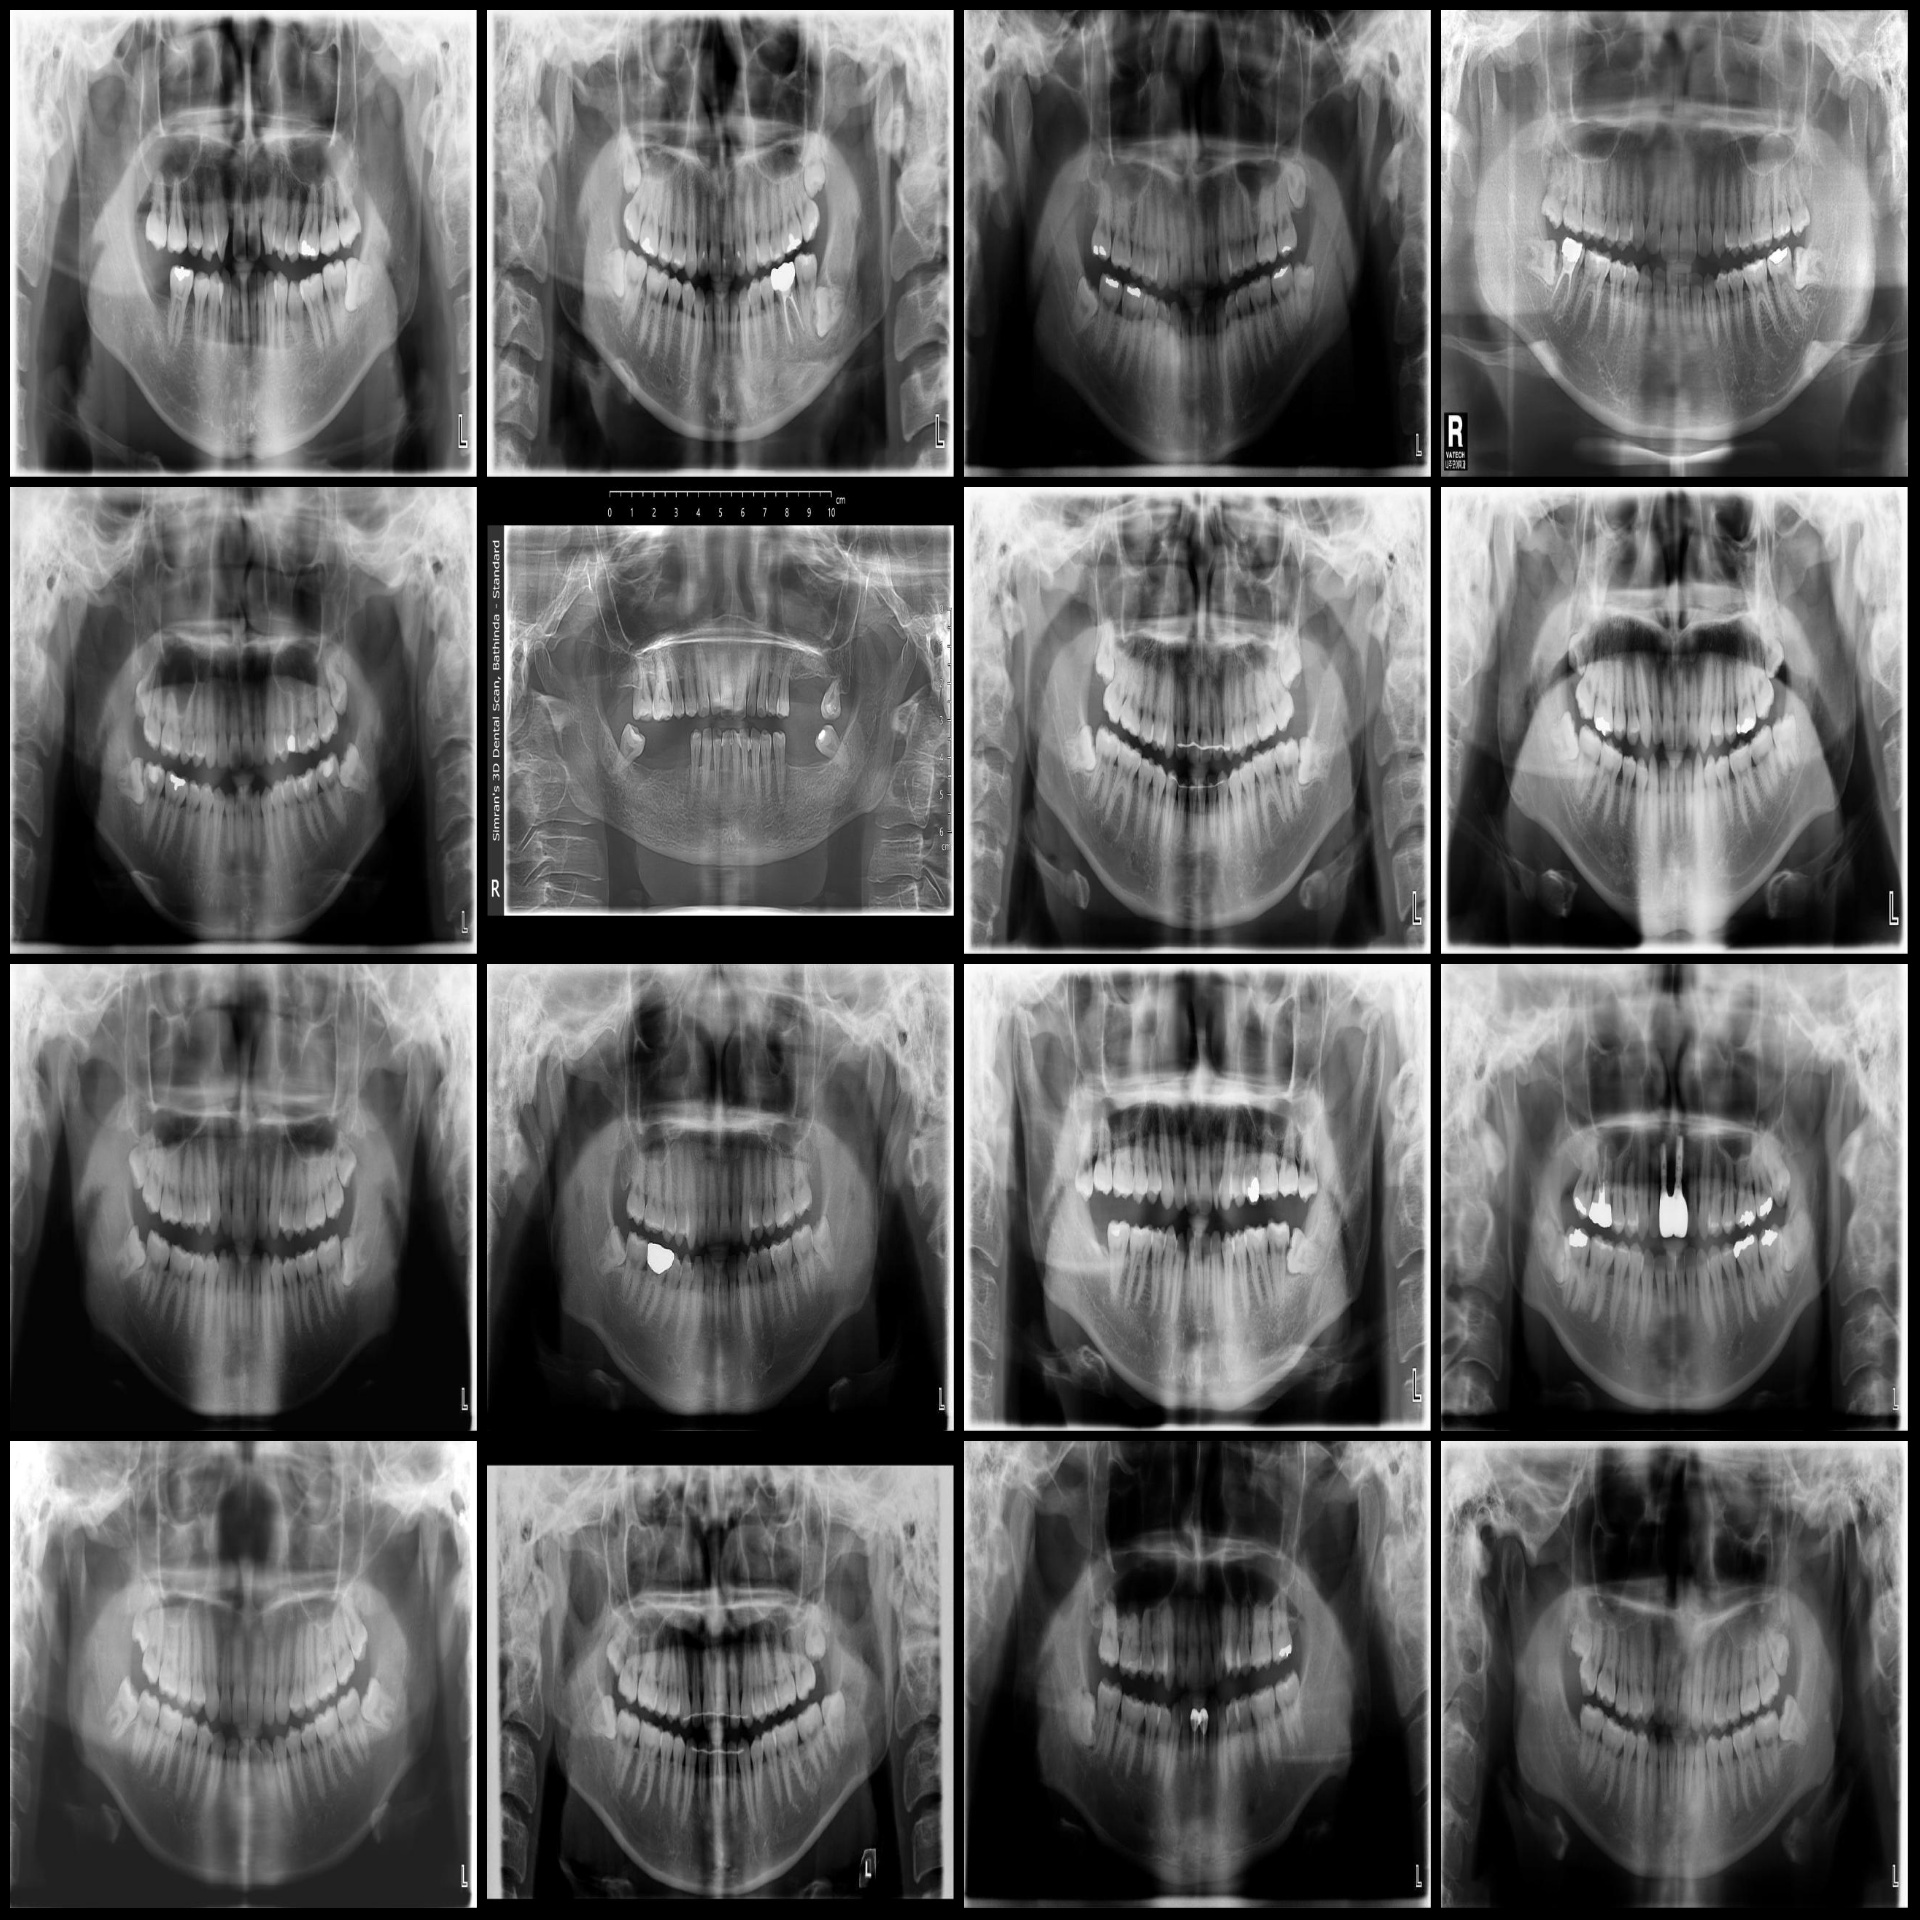

原图(随机选16张图):